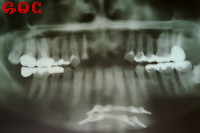

南雲先生に診てもらうと事故により前歯を失ってから時間が経過しているために上顎の歯茎が退縮しているとのことでした(事故により歯だけでなく周りの骨も失った)。

▼治療前![]() |

その状態ですぐにインプラントを埋め込むと、長い不自然な歯を入れることになってしまうと言われました。歯の見えている部分は骨からの距離であるため、歯を長くしないといけなくなるのです。

そこでまずは骨と歯茎の造成を行いました。

その手術が終わり半年後くらいして落ち着いた段階で、上顎前歯に3本のインプラントを埋め込みました。